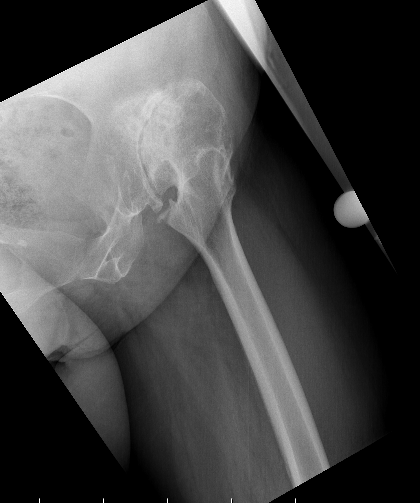

Cerebral Palsy

Issues

- spasticity / joint contractures

- hip subluxation /dislocation preoperatively

- dysplastic femoral head / acetabulum